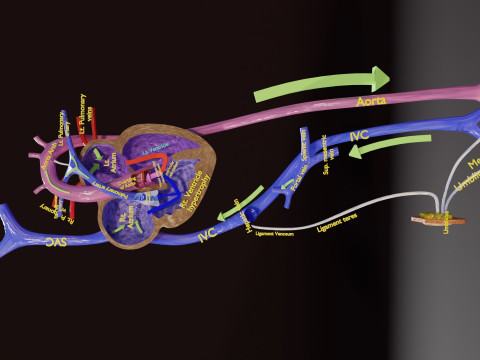

The model meshes include adult circulation versus circulation in Tetralogy of Fallot (TAF), arrow labels and text labels. The blood flow in a patient with Tetralogy of Fallot is outlined in this model. To contrast it to normal blood circulation a separate model of normal circulation is included. The Tetralogy of Fallot (OVER RIDING OF AORTA, PUL STENOSIS, VENTRICULAR SEPTAL DEFECT, RIGHT VENTRICULAR HYPERTROPHY), fossa, ligament teres , venosus, and arteriosus are duly depicted with proper labelling and blood flow directional arrows. Excellent model for teaching, demonstration and knowlegde of human body. The models include both procedural and image textures blend files separately. The texture file include diffuse, roughness and normal png and jpeg based on non overlapping UV maps.